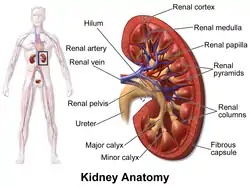

Vertical section of kidney. (Label "medullary sub." visible near top.) Kidney anatomy, with pyramids labeled at right

The renal medulla (Latin: medulla renis 'marrow of the kidney') is the innermost part of the kidney. The renal medulla is split up into a number of sections, known as the renal pyramids. Blood enters into the kidney via the renal artery, which then splits up to form the segmental arteries which then branch to form interlobar arteries. The interlobar arteries each in turn branch into arcuate arteries, which in turn branch to form interlobular arteries, and these finally reach the glomeruli. At the glomerulus the blood reaches a highly disfavourable pressure gradient and a large exchange surface area, which forces the serum portion of the blood out of the vessel and into the renal tubules. Flow continues through the renal tubules, including the proximal tubule, the loop of Henle, through the distal tubule and finally leaves the kidney by means of the collecting duct, leading to the renal pelvis, the dilated portion of the ureter.

Renal pyramids (or malpighian pyramids or Malpighi's pyramids named after Marcello Malpighi, a seventeenth-century anatomist) are cone-shaped tissues of the kidney. In humans, the renal medulla is made up of 10 to 18 of these conical subdivisions.[4] The broad base of each pyramid faces the renal cortex, and its apex, or papilla, points internally towards the pelvis. The pyramids appear striped because they are formed by straight parallel segments of nephrons' Loops of Henle and collecting ducts. The base of each pyramid originates at the corticomedullary border and the apex terminates in a papilla, which lies within a minor calyx, made of parallel bundles of urine collecting tubules.

The renal papilla is the location where the renal pyramids in the medulla empty urine into the minor calyx in the kidney. Histologically it is marked by medullary collecting ducts converging to form a papillary duct to channel the fluid. Transitional epithelium begins to be seen.